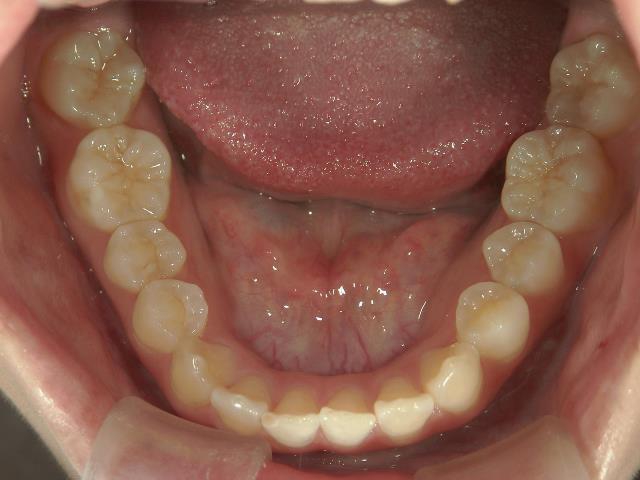

矯正歯科 治療前 下顎